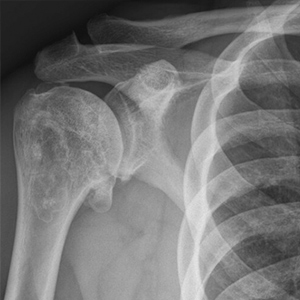

74 year young female who underwent Anatomic Total Shoulder Arthroplasty